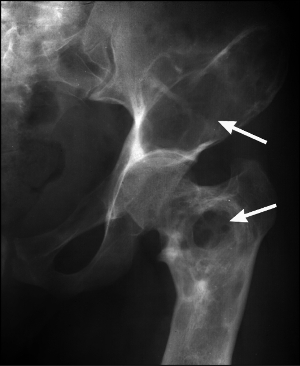

Субхондральный остеосклероз (поражение суставных поверхностей) выступает рентгенпроявлением артроза.

Субхондральный остеосклероз суставных поверхностей – это подхрящевая форма.

Костная ткань в момент повреждения хрящевого слоя, покрываемого суставные поверхности, уплотняется и разрастается в процессе развития. На ее поверхности образуются остеофиты — наросты, выполненные из костной ткани. Описанные остеообразования иногда могут располагаться на самом краю хряща и совершенно не препятствовать движению. Однако, в другом случае наросты прорастают между поверхностями диартроза и сужают суставную щель. Тогда суставная двигательная способность нарушена и во время функционирования может сопровождаться болевым ощущением.